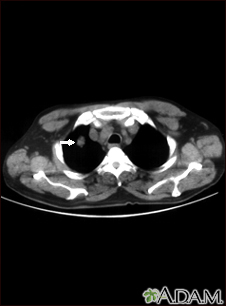

Pulmonary nodule, solitary - CT scan